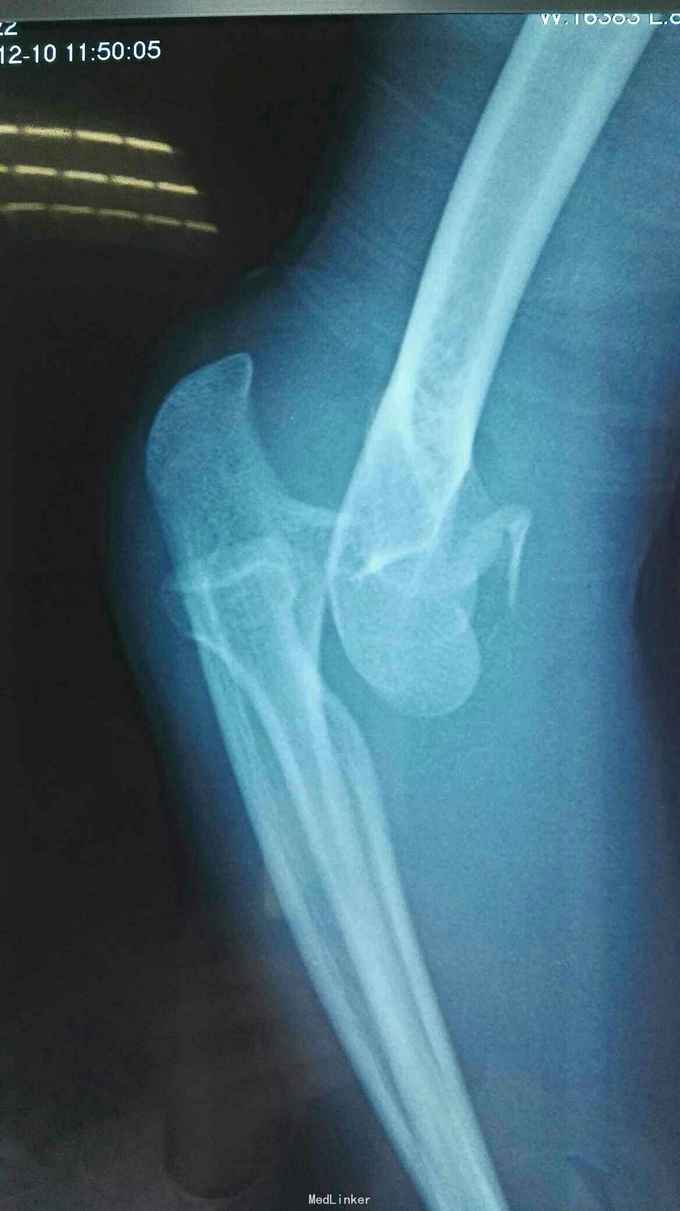

右肘跌伤疼痛伴不能活动1天。 患者,男,14岁,1天前跌倒,感右肘部剧痛,不能活动,急送当地医院拍片示:右肘关节脱位,尺骨冠狀突骨折,右桡骨小头骨折,行手法复位,今来我院就诊。

查体:右肘关节高度肿胀,触痛,活动功能障碍手指末端感觉血运正常。 辅查:x线,CT:右肘关节脱位,右尺骨冠突骨折,右桡骨小头骨折

诊断:右肘恐怖三联症。 治疗:伤后第6天在全麻下行右肘恐怖三联症切开复位内固定术,术中先取肘外侧弧形切口,显露桡骨头,用2枚埋头螺钉固定桡骨头,见右肘外侧副韧带尺侧束断裂,用锚钉固定外侧副韧带。取右肘内侧弧形口,显露冠状突,见冠状突骨折块很小,移位较远,复位,2枚螺钉固定,内侧副韧带前束断裂,修补,术后石膏因定。